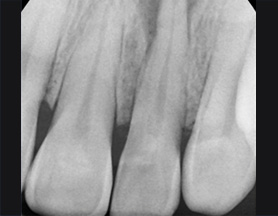

뿌리에 염증으로 흔들리는 치아

치주 치료로 재생된 건강한 잇몸

치주염은 잇몸의 뼈 부분까지 염증이 진행된 상태를 말합니다. 치석이 치주염 상태가 될 때까지, 즉, 치아 뿌리까지 들러붙어 내려가게 되면

치주인대가 소실되고 치조골까지 녹아 내리게 됩니다. 고운미소에서는 증상이 악화되기 전에 큐렛, 근관치료, 치근단 수술,

치아 재식술등의 다양한 치료로 치아를 최대한 살리려고 노력하고 있습니다.